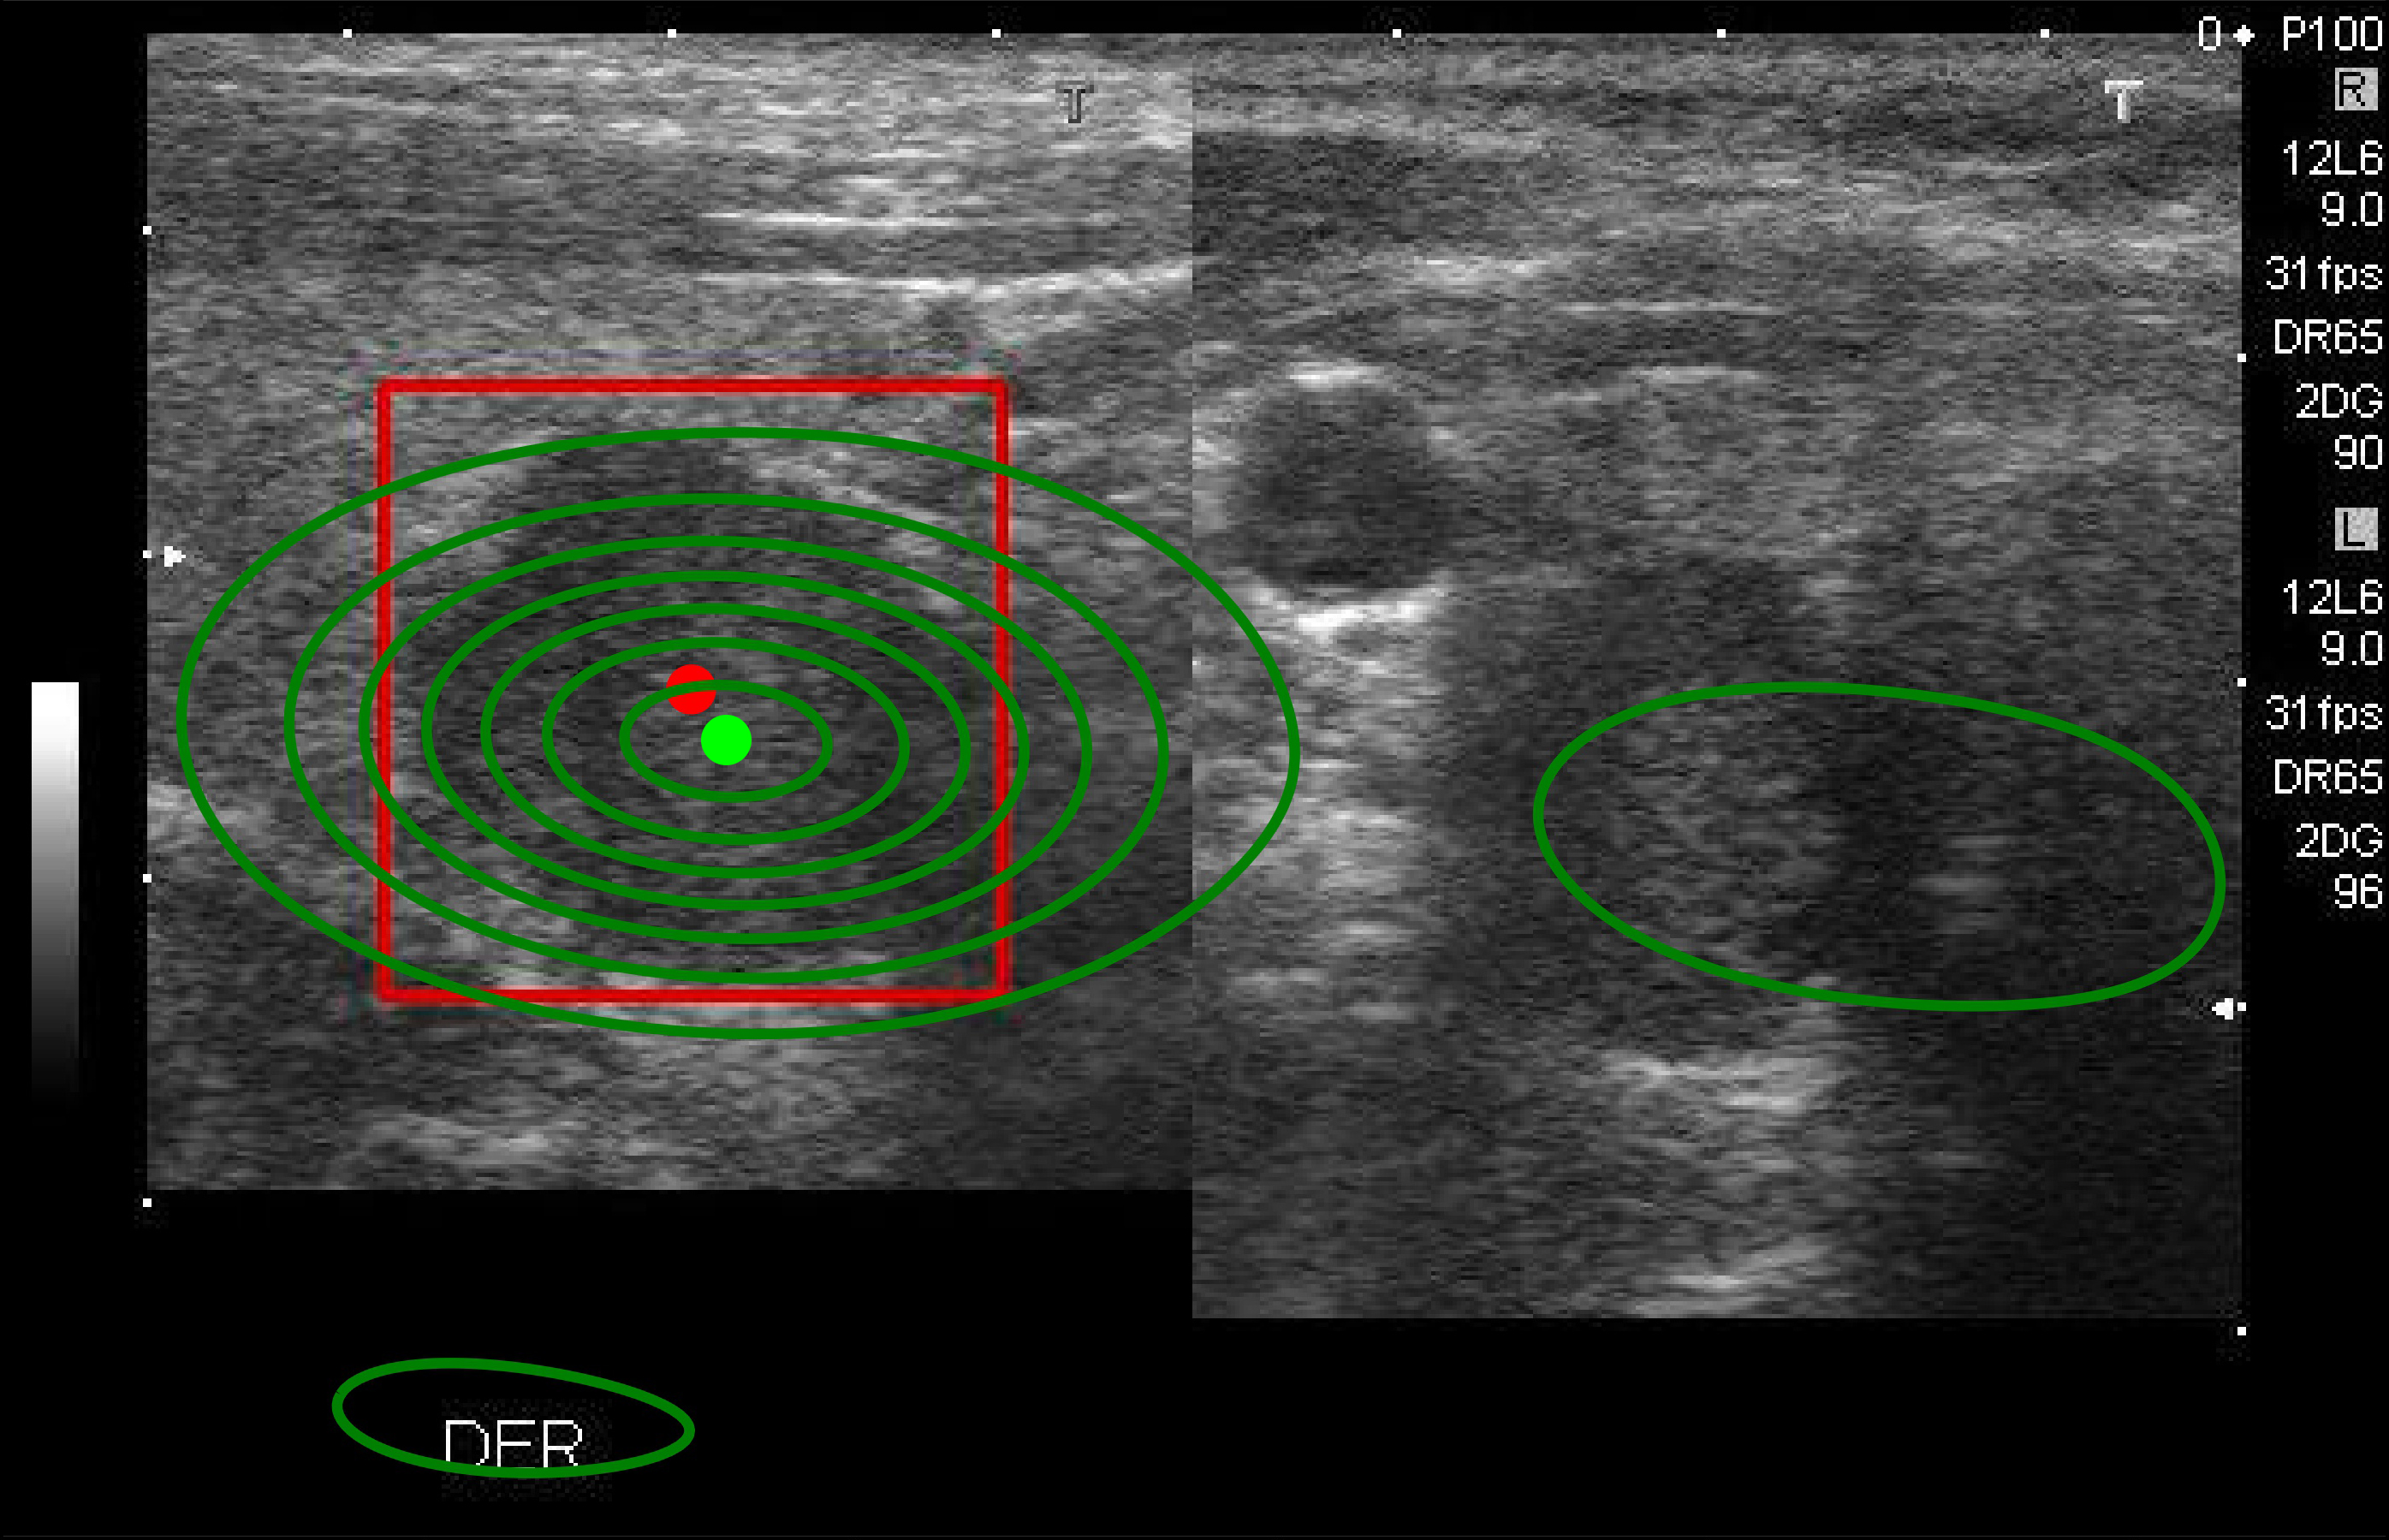

KDE creates a distribution density map by weighting distances of all data points for each specific location along the distribution. If more data points are grouped locally, the estimation is higher as the probability of seeing a point at that location increases.

In the object detector’s first stage, we apply KDE to the center points of 300 independent and identically distributed boxes to obtain the distribution density map given by:

where is called the kernel function that is generally a smooth, symmetric function such as a Gaussian and called the smoothing bandwidth controls the amount of smoothing.

We represent the distribution density map as multiple continuous probability density curves on the image. The KDE score of a point is computed as the log-likelihood of that point under the KDE model. The score reflects the likelihood that any given box has been drawn from the learned probability distribution. The higher the KDE score is, the more the given box matches the distribution.

The prediction’s consistency KDE (PCKDE) is computed as the ratio between the KDE score of the final box’s center point detected by the model and the KDE score of the point achieving the highest probability value on the distribution density map. Finally, we set the threshold as 0.5 to grade the PCKDE score. If the PCKDE score exceeds 0.5, the model’s detection is considered consistent, as shown in Fig. 3 and non-consistent in Fig. 3a.

[Consistent (PCKDE=0.934)]